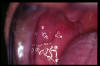

CM Puntos de Fordyce